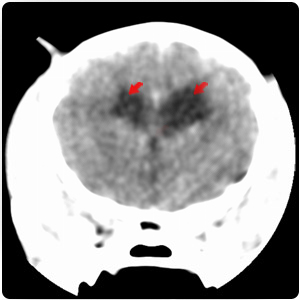

側腦室非對稱性中度擴張

第三四腦輕微擴張 |